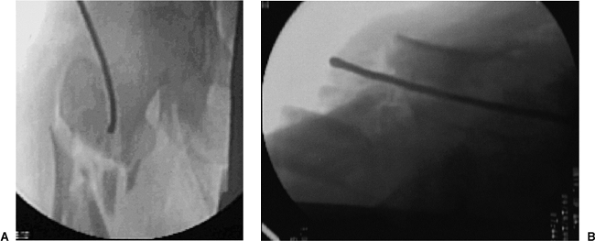

![]() |

Figure 20.7. A,B. For correct entry portal, the guide wire should be overreamed with an 8-mm cannulated rigid reamer.

Figure 20.8. A,B. A 3.2-mm guide wire is inserted into fracture site. The tip of wire is bent to facilitate fracture reduction.

ball-tipped guide wire is bent at its tip. The wire is advanced to the

level of the fracture with the curve opposing the medial cortex. Its

position is confirmed within the femur by AP and lateral views taken

with the image intensifier (Fig. 20.8). The proximal fragment is reduced to the distal fragment manually or with an internal fracture-alignment device (Fig. 20.9).